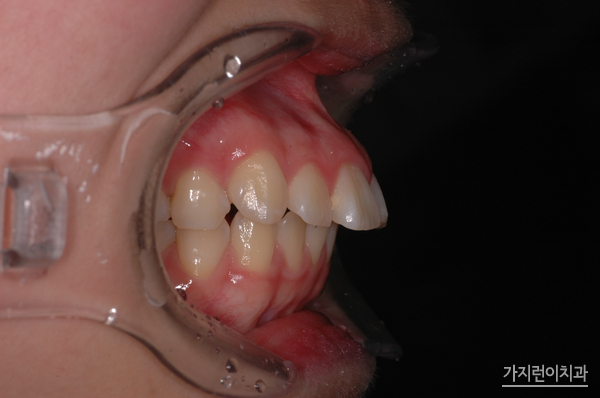

잇몸이 드러나는 거미스마일. 전문가에 따르면 위 턱뼈의 전방 부위가 수직이나 수평으로 과성장하는 골격 성장 때문에 발생하는데요. 골격성장뿐만 아니라 치아에도 원인이 있어 교정을 통해 개선해볼 수 있습니다. 웃을 때 윗 입술을 기준으로 잇몸이 3mm 이상 노출이 되면 거미스마일로 분류되고 있는데요. 원인별 치료법은 다르지만 치아나 잇몸의 돌출 때문이라면 치아와 잇몸을 안쪽으로 이동시키는 방법을 진행하게 됩니다. 따라서 원하는 부위에 미니스크류를 식립해 치아를 이동시키는 경우도 있는데요. 중요한 것은 힘의 크기와 방향의 조절입니다.

많은 경우 돌출입이 있으면 거미스마일을 가진 경우가 많습니다. 입을 다물 때 입매가 부자연스럽거나 심한 경우에는 치아가 제대로 맞물리지 않아 저작이 어려운 경우도 있는데요. 기능적인 문제가 생기게 된다면 단순히 미적으로 아름답지 않다고 하는 불평을 넘어 비수술 치아교정만으로도 개선방법을 찾아야 합니다. 사실 돌출입 교정의 경우 시간이 오래 걸리는 것으로 알려져 있는데요. 튀어나온 치아와 잇몸까지 서서히 안쪽으로 밀어넣는데 시간이 걸리기때문입니다.

위 환자분들의 경우 1년 8개월의 대장정 끝에 치료과정이 끝나셨습니다. 상하악의 이동을 잘 조절해 골격적인 밸런스도 마무리되셨는데요. 치아교정을 전문적으로 다루고 있는 서울가지런이치과 교정과 의원인만큼 심한 거미스마일 증상과 돌출입 증상도 무리없이 해결했답니다. 오래도록 안정된 결과를 누리고 있는 이 케이스! 걱정말고 서울가지런이치과 교정과 의원을 방문해 보시기 바랍니다.